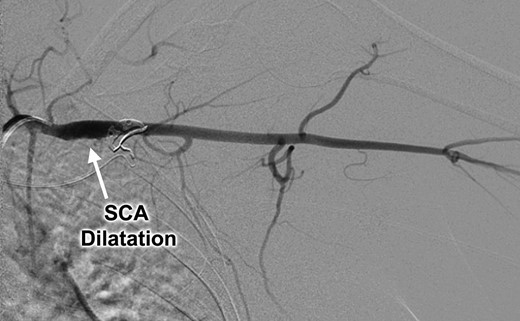

An otherwise healthy 44-year-old female nurse presented with a painful left arm and hand, 2 weeks after she had fallen onto the outstretched left arm while hiking. She sought medical attention when she developed Raynaud’s phenomenon and was unable to feel pulses at the wrist, and clinical evaluation suggested thrombosis of the left brachial, radial and ulnar arteries. Contrast-enhanced computed tomography (Figs 1 and 2) and catheter-based arteriography (Fig. 3) confirmed the diagnosis and showed that while there was no cervical rib or other bony abnormality, there was focal stenosis of the left subclavian artery at the level of the first rib with mild post-stenotic dilatation. These findings indicated that the subclavian artery was the source of thromboembolism and the patient was successfully treated with catheter-based thrombolysis to resolve the acute obstruction. She was discharged on a direct oral anticoagulant but returned within several weeks after recurrence of symptoms. She was found to have rethrombosis and again underwent thrombolysis, followed by anticoagulation with an alternative agent, and was then referred to our specialized TOS center for surgical treatment.

Catheter-based left subclavian arteriogram demonstrating post-stenotic aneurysmal dilatation of the subclavian artery (SCA).

Clinical evaluation revealed an absence of palpable pulses at the left wrist but adequate arterial circulation to the hand at rest, with brisk capillary refill in the fingers and no signs of digital embolism. Upper extremity strength, sensation and range of motion were normal and there were no signs of swelling, edema or cyanosis to suggest venous obstruction. The patient was brought to the operating room for thoracic outlet decompression using a left supraclavicular approach. After mobilizing and rotating the scalene fat pad on a lateral pedicle, the phrenic nerve was identified in its expected position on the surface of the anterior scalene muscle; however, the subclavian artery was not found within the scalene triangle adjacent to the brachial plexus, but in front of the anterior scalene muscle insertion on the first rib, in the costoclavicular space directly posterior to the phrenic nerve (Figs 4 and 5). Thoracic outlet decompression was performed with anterior and middle scalenectomy, brachial plexus neurolysis and first rib resection [10]. Direct inspection and intraoperative left upper extremity arteriography demonstrated post-stenotic dilatation of the subclavian artery and chronic occlusion of the brachial artery with abundant collaterals. The affected segment of the subclavian artery was resected and found to contain an ulcerated lesion with thrombus (Fig. 6), and the artery was reconstructed with a 6-mm diameter cryopreserved femoral artery interposition graft (Fig. 7). The patient was discharged on postoperative Day 3 taking a direct oral anticoagulant and she was clinically stable during subsequent follow-up.